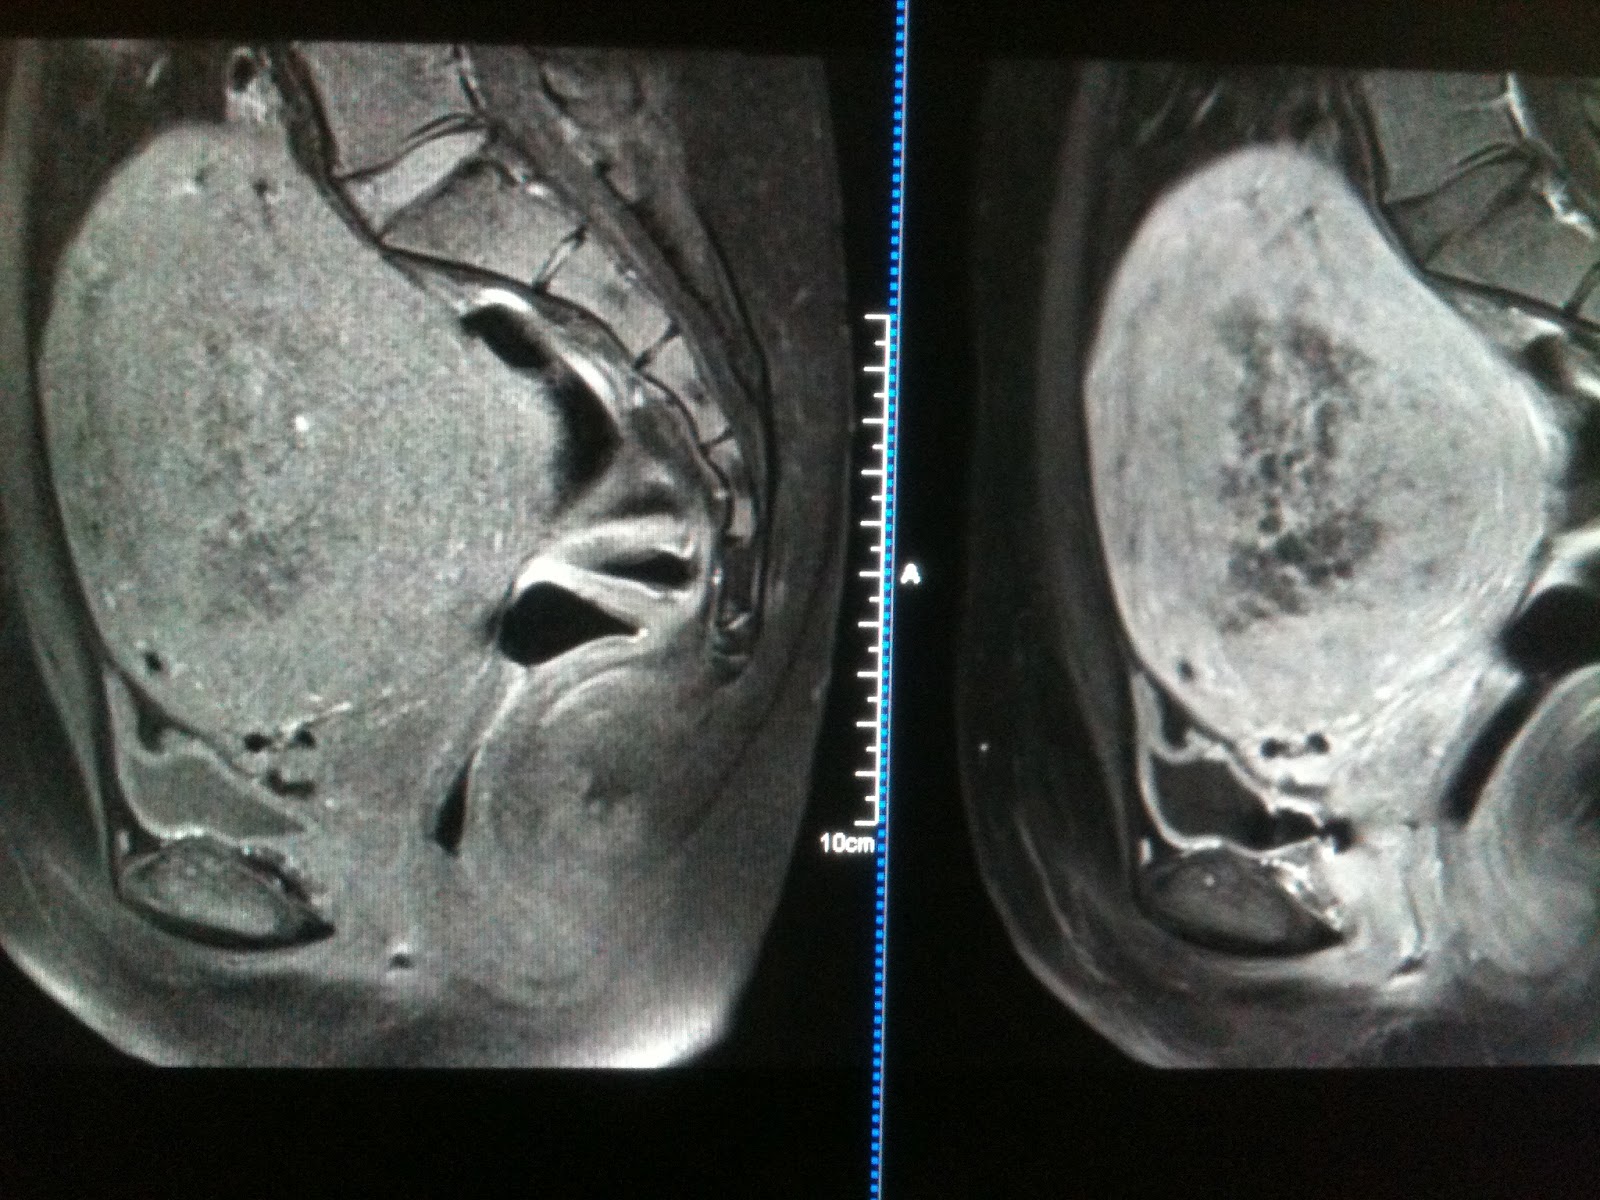

From ar.iiarjournals.org

Figure 1. Endometrial Adenocarcinoma Presenting as Hematometra with Does A Thickened Endometrial Lining Mean Cancer It can cause vaginal bleeding. Itendometrial cancer is now more than 40 years since the publication of the first reports of an association between use of estrogenestrogen. Transvaginal ultrasound (tvus) represents an accurate and noninvasive technique to investigate endometrial thickness (et) in the. Endometrial hyperplasia is a condition in which the lining of your womb becomes too thick. Endometrial hyperplasia. Does A Thickened Endometrial Lining Mean Cancer.

From www.indianradiology.com

Endometrial Hyperplasia Versus Endometrial Cancer Sumer's Radiology Blog Does A Thickened Endometrial Lining Mean Cancer In some women, this can. This may cause uncomfortable symptoms for women, including heavy. Endometrial hyperplasia is a thickening of the endometrium which is the womb (uterus) lining. It can cause vaginal bleeding. Endometrial hyperplasia is a condition in which the lining of your womb becomes too thick. Transvaginal ultrasound (tvus) represents an accurate and noninvasive technique to investigate endometrial. Does A Thickened Endometrial Lining Mean Cancer.